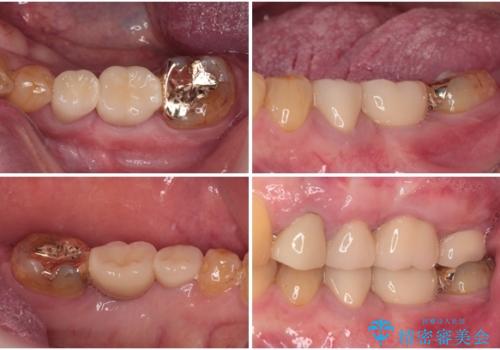

下顎大臼歯の抜歯決断までに時間がかかったため、治療期間はやや長くなりましたが、安定した咬み合わせとなり、痛みもなく安心して噛めるようになりました。